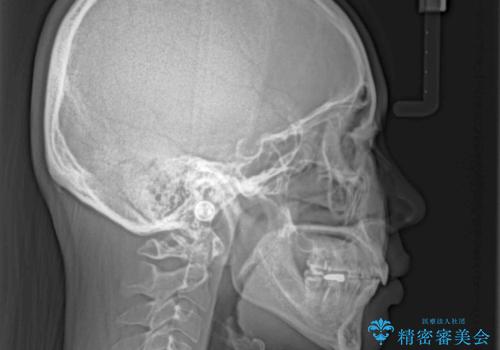

抜歯矯正で唇を閉じやすく ワイヤー矯正

- 口元の閉じにくさと、前歯のでこぼこの歯並びを気にして来院された患者様です。

口元を積極的に引っ込めるために、上下左右の小臼歯計4本を抜歯することとしました。

4本の歯を抜歯したことで、飛び出していた口元が引っ込み、横顔が大きく改善されました。